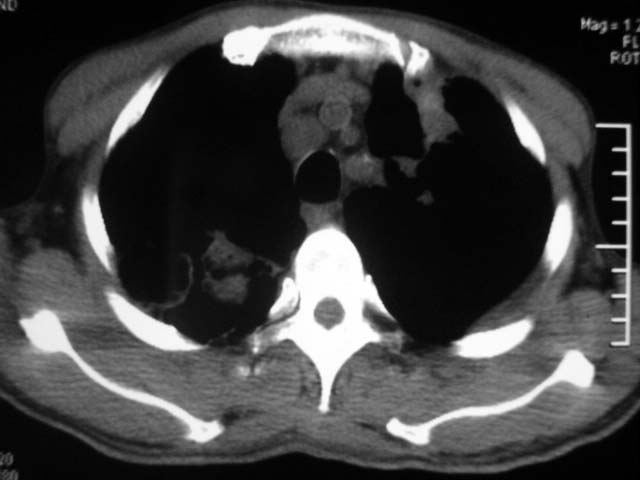

男,52岁,发热2月,糖尿病史。

抗结核治疗irpz方案,血糖未治疗,空腹15.9左右。症状无好转,左胸痛。

复查ct

2、双肺见多发片状及结节状高密度影,大多数病灶中心均见“空泡征”。

3、纵隔内淋巴结肿大。

结果:两肺继发性肺结核并曲霉菌感染。